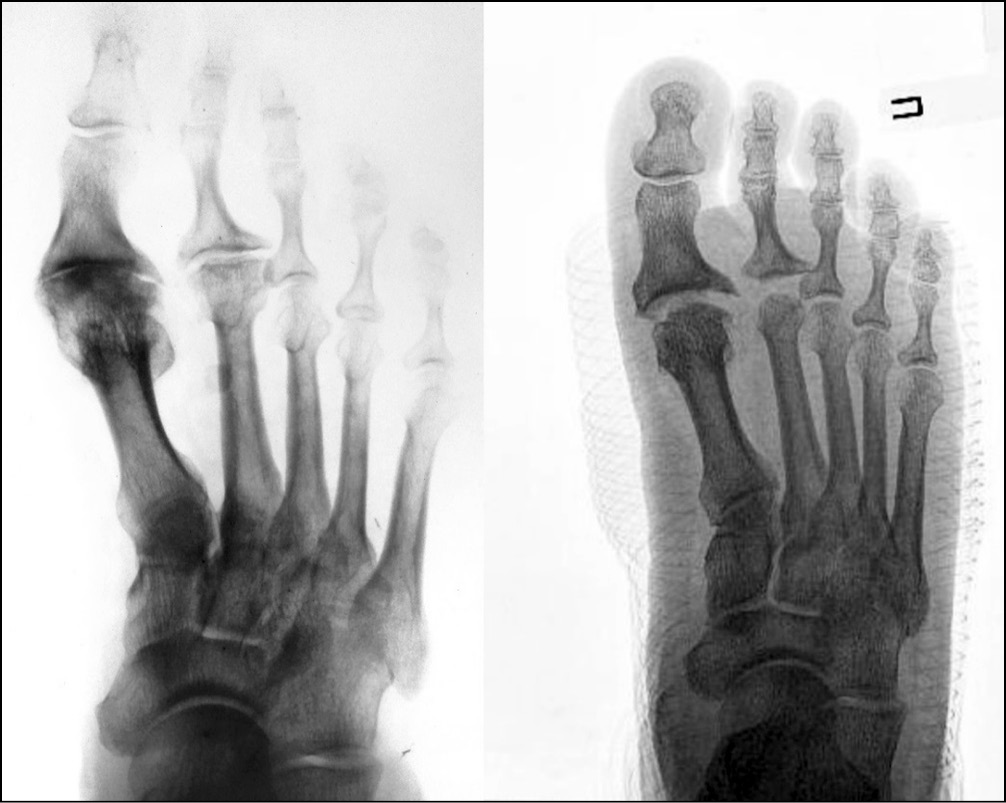

Рентгенография стоп после операции демонстрировала значительное увеличение суставной щели I ПФС (рис. 11). Однако при контрольном осмотре через 3 мес. и далее наблюдали незначительное сужение суставной щели. Тем не менее клинически данное явление не проявлялось снижением ROM. Напротив, пациенты с 3 по 12-й месяц после операции в целом отмечали увеличение ROM (рис. 10, 12).

Рис. 11. Рентгенограмма стопы до и в первые сутки после хондропластики I и II плюснефаланговых суставов